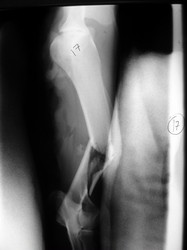

Fijación Externa

Fijación externa en IVOT

PRÁCTICAS CURSO DE FIJACIÓN EXTERNA PERFECCIONAMIENTO.

Húmero.